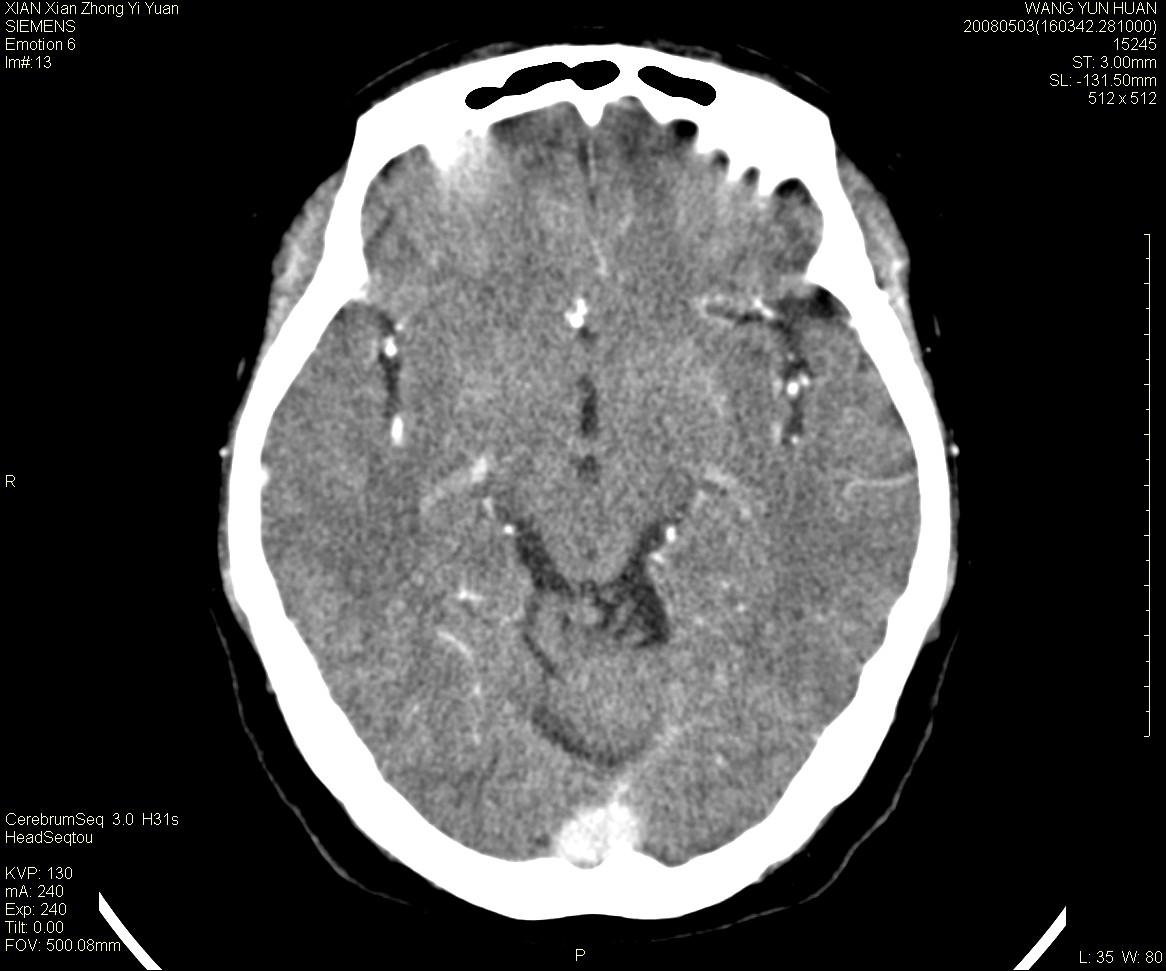

病灶显示轻度强化,ct增加4hu左右,大家看是什么肿瘤.

强化后动脉期及延迟2分钟,五分钟图像

小脑蚓部囊型肿块,内有实性结节及钙化点。增强后囊壁及结节轻度强化。

考虑蚓部星形细胞瘤(ⅱ级可能性大)。

小脑蚓部肿块,周围无明显占位效应及水肿带,增强轻度强化,考虑低分级星形细胞瘤。

小脑吲部胶质瘤(少枝胶质细胞瘤或形星细胞瘤)

考虑动静脉畸